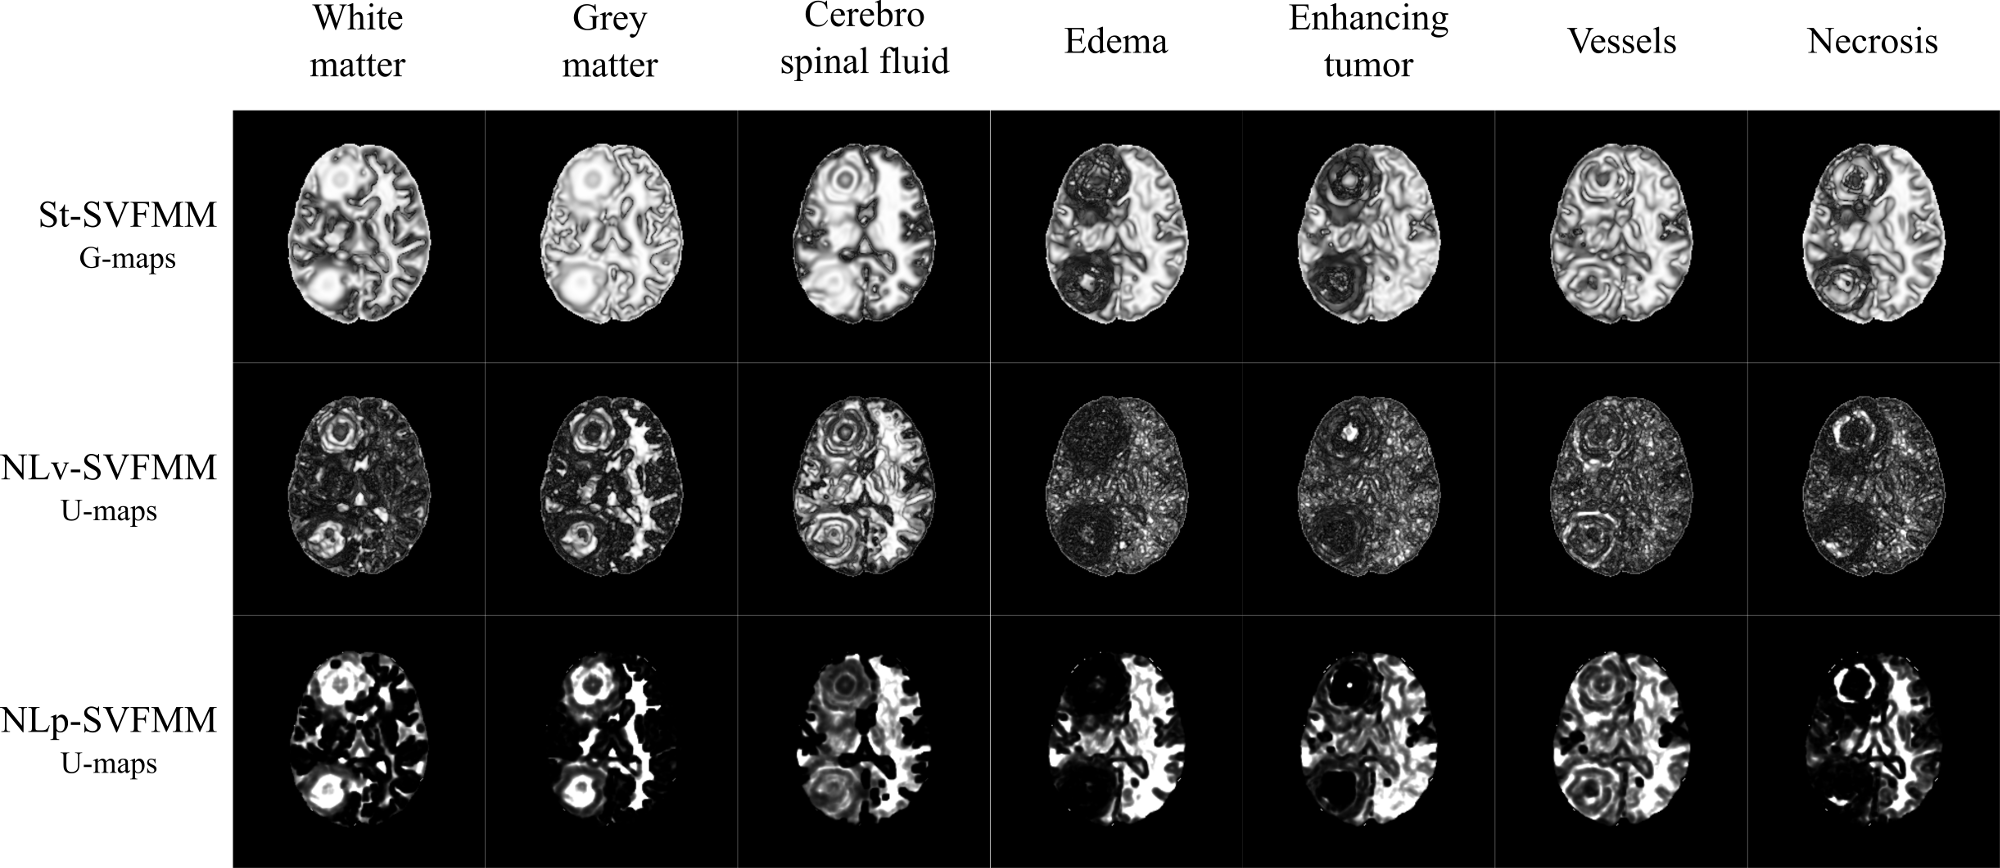

Comparative study of unsupervised learning algorithms for glioblastoma segmentation

In this study, a comparison of unsupervised learning algorithms, including structured and non-structured methods was performed for the task of high grade glioma segmentation. The study describes the statistical model underlying each algorithm and also proposes a general post-processing stage to identify which classes of an unsupervised segmentation correspond to pathological or healthy tissues. An independent evaluation of the performance of the unsupervised learning algorithms was carried out in a public real dataset, which demonstrated the capability of unsupervised learning to extract relevant knowledge from MRI data. This work was published in the journal contribution P1 (Juan-Albarracín et al, 2015b) and presented in the conference P2 (Juan-Albarracín et al, 2015a).

An unsupervised learning algorithm for structured prediction

A new variant of the Spatially Varying Finite Mixture Models (SVFMMs) family is proposed in this thesis. The algorithm, named Non Local Spatially Varying Finite Mixture Model (NLSVFMM), successfully merges the SVFMMs with the Non Local Means (NLM) framework, proposing a continuous Markov Random Field (MRF) that simultaneously enforces smooth constraints in homogeneous regions of the image while preserves the edges and structures without degradation. This approximation improves the existing approaches in terms of complexity of the model, as the NLM weighting function does not introduce additional parameters into the model to be estimated. Moreover, it outperforms current methods in terms of performance in a segmentation task of real world images. This work was published in the journal contribution P3 (Juan-Albarracín et al, 2019b).